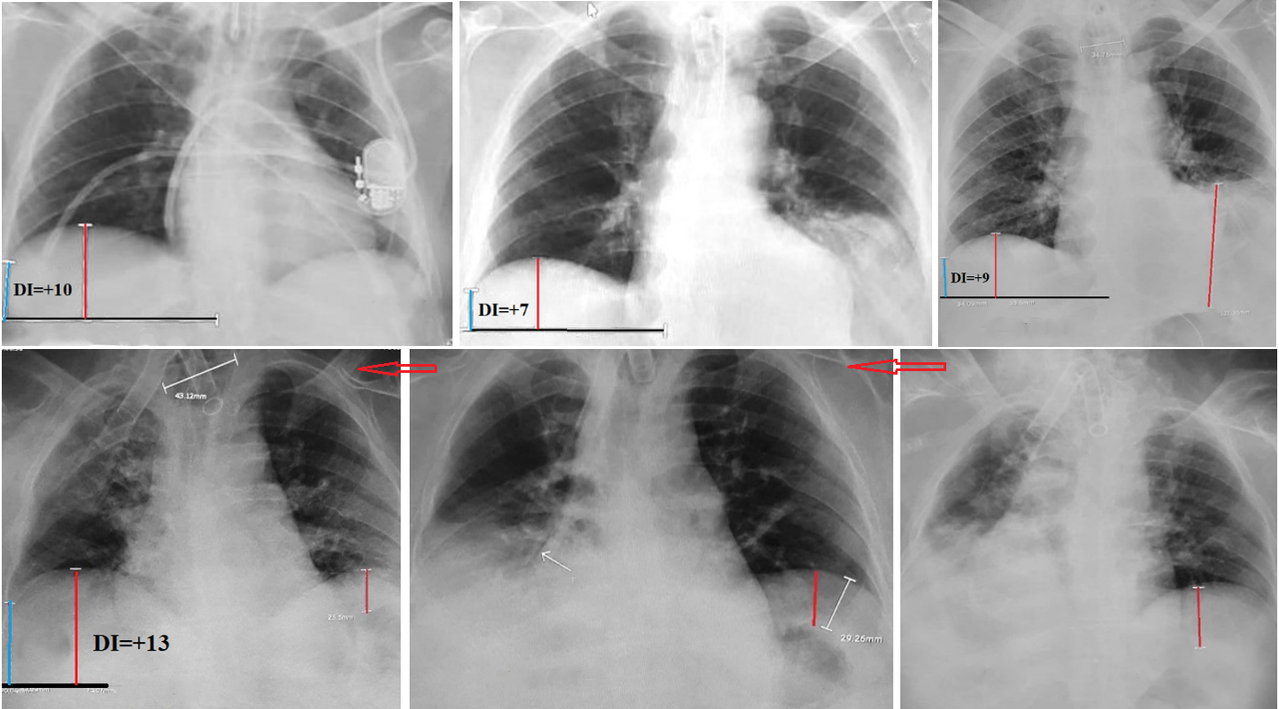

Atelectasis at the Bases of Both Lungs

Nineteen patients were admitted with a diagnosis of bilateral recurrent pneumonia; however, in all cases, radiographic evidence of atelectasis was already present on admission. In 13 cases (68%), the diagnosis of bilateral atelectasis was possible only based on DI > 5, which ranged from 6 to 14 (mean 9.8). This indicated a marked reduction in lung volume despite both diaphragmatic domes being at the same level (Figure 4a, d). In three cases, the right hemidiaphragm was significantly higher than the left (Figure 4e). Nevertheless, dynamic imaging (Figure 4d–f) demonstrated a substantial reduction in the volume of both lungs on all radiographs. Atelectasis of the left lung was further supported by a significant distance between the left hemidiaphragm and the gastric air bubble in five patients (Figure 4c–f, red line), whereas normally the gastric bubble lies directly beneath the diaphragm. In three additional cases, the left hemidiaphragm was higher than the right, but no hyperinflation of the right lung was observed. Instead, the right lung volume was below normal, as indicated by a DI > 5. In at least 13 (68%) of the 19 patients with bilateral atelectasis and symmetrical diaphragm position, all conventional radiographic signs of atelectasis were absent. Only a marked reduction in lung volume, quantified by DI, enabled correct diagnosis, which was subsequently confirmed during follow-up.

Figure 4. Radiographs of patients admitted with bilateral atelectasis. (a). In a patient with tracheal intubation, shows inflammatory changes above the diaphragm on both sides, but there are no typical signs of atelectasis. The right dome of the diaphragm is slightly higher than the left, as is normal. DI = +10 indicates a significant decrease in the volume of the right lung due to atelectasis. (b, c). A sharp rise of the left diaphragm does not raise doubts about atelectasis on the left. However, it is not accompanied by hyperventilation of the right lung. The volume of right lung is clearly reduced, since DI> 5. (d, e, f). The patient was admitted with a diagnosis of recurrent pneumonia. Despite the radiographic conclusion about bilateral atelectasis, he received antibiotics for 4 months after each attack of shortness of breath accompanied by high fever. Since these cases were considered aspiration of food or gastric contents, doctors gradually inflated the balloon on the tracheostomy tube, increasing its diameter to 4 cm (see d). In Figure 3e, the arrow indicates bronchiectasis containing air after infected mucus was expelled into the bronchi of the right lung. Atelectasis of the left lung is suggested by both the decreased lung volume and the distance between the left dome of the diaphragm and the gastric bubble.